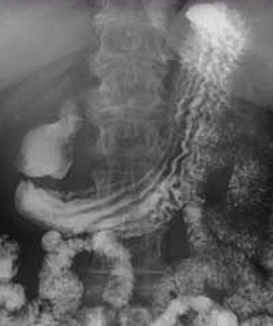

| images TOGD de oesophage

normale |

image TOGD de oesophage (

angle de His ) et estomac normale |

Images normales de estomac , bulbe et

duodenum expose en serie |